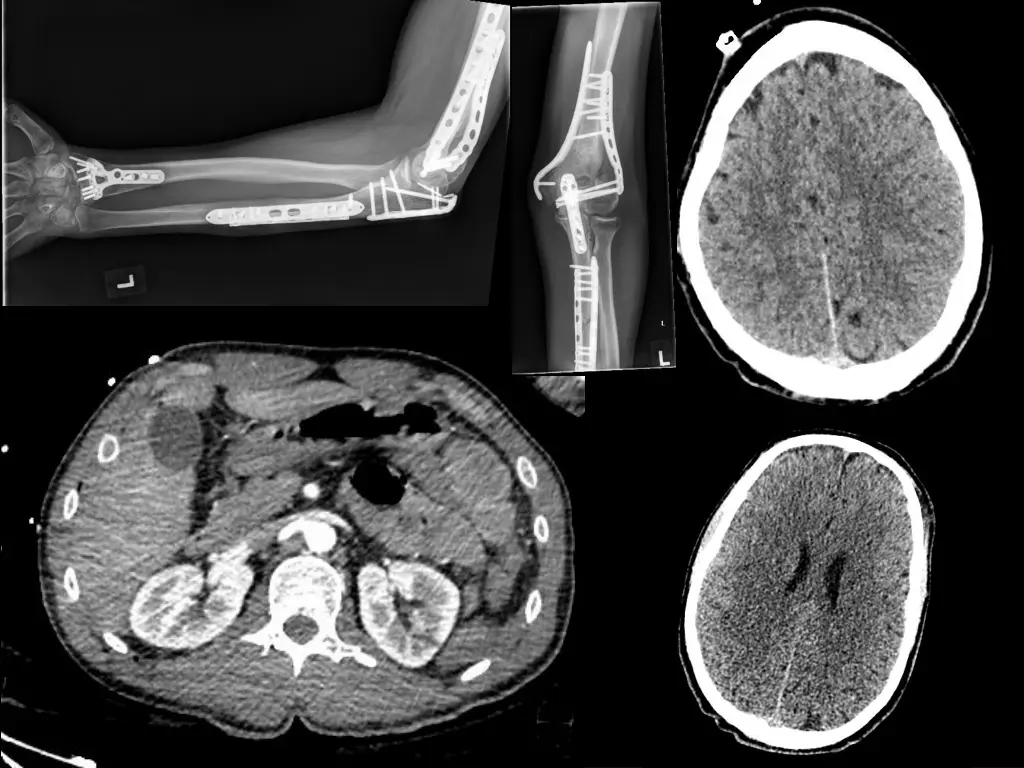

Admission to Intensive Care Neurocritical care Intracrainial Pressure monitor Sedated and ventilated Increasingly unstable CT Scan

Intensive Care Theatre Repair of small bowel perforation Returned to ICU 24hrs to stabilise, reducing organ support Extubated Discharged from ICU to Major Trauma Ward